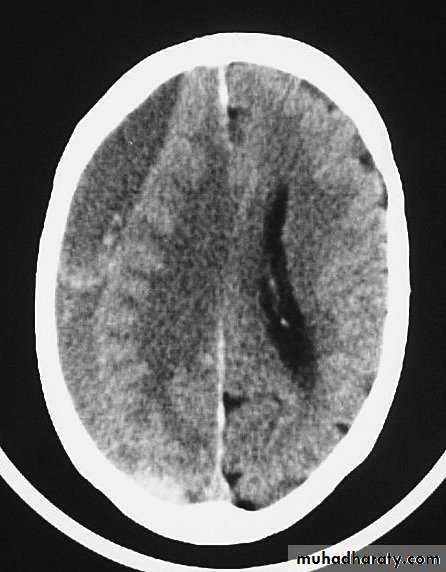

Acute Subdural Haematoma

Usually due to MORE SEVER high velocity trauma and thus associated with a poorer outcome.

Source of bleeding (haematoma): include:

Most result from torn bridging veins or focal tears of a cortical artery.

Cortical lacerations or contusions.

Bleeding from tears in the dural venous sinuses.

Clinical Picture: patient will present with a picture similar to that of an extradural haematoma, but there is persistent loss of consciousness with no lucid interval.

Ct scan will show a concave hyperdence collection because blood follows the subdural space over the convexity of the brain.

Acute Subdural Haematoma are rapidly evolving lesions and early evacuation via craniotomy is mandatory.